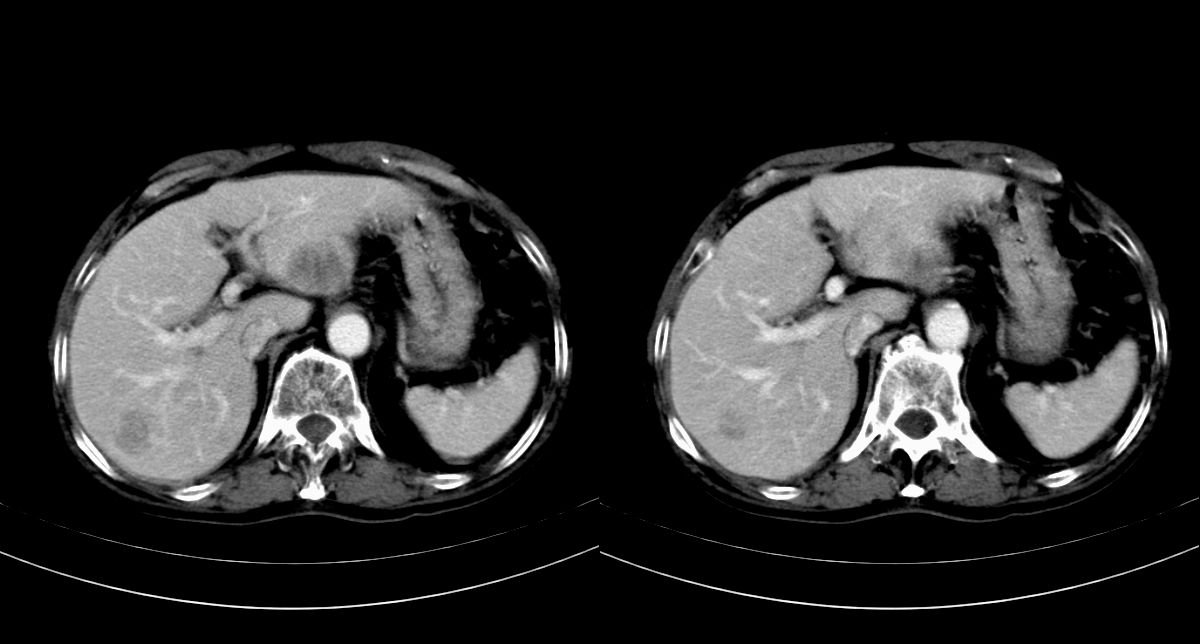

男,79y,无不适。体检发现肝脏占位。

肝内多发低密度结节,增强动脉期明显强化,门脉期逐渐下降,内有液化坏死区。

肝内多发低密度结节灶,增强动脉期明显不规则环状强化,;门脉期逐渐下降,肿瘤壁厚薄不一,内有坏死液化区。